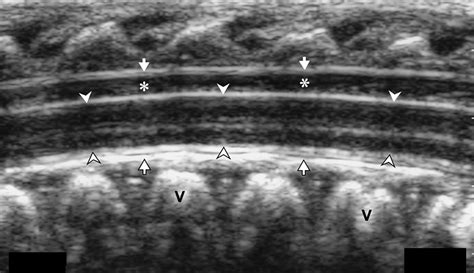

• Identify the Insertion Site: Palpate the spine to identify the L3-L4 or L4-L5 interspace, which is the most common site for lumbar puncture in neonates.

• Insert the Needle: Insert the spinal needle at a 90-degree angle to the skin, aiming towards the umbilicus. Advance the needle slowly until a "pop" is felt, indicating entry into the subarachnoid space.